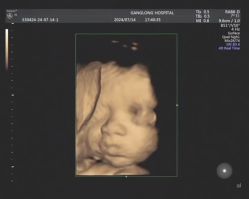

• -深圳港龙妇产医院

相册

微笑少年 上传于 25-09-05 | 报错